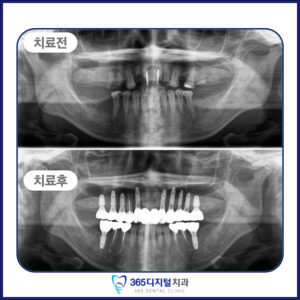

임플란트는 단순히 인공치아를 심는 것이 아닌,

환자의 삶의 질을 회복하는 진료라고 생각합니다.

오직 정밀한 진단과 정직한 진료만이

좋은 결과로 이어진다는 믿음으로

한 케이스, 한 환자에 깊이 집중합니다.

계획된 진단과 세밀한 설계,

그리고 환자 개인의 구강 구조에

맞춘 접근이 중요합니다.